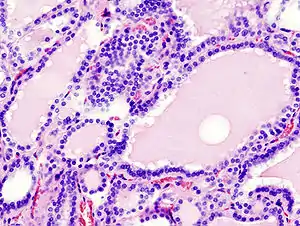

![]() Дифузна гіперплазія тканини щитоподібної залози, що характерно для гіпертиреозу (фарбування гематоксиліном-еозином) Дифузна гіперплазія тканини щитоподібної залози, що характерно для гіпертиреозу (фарбування гематоксиліном-еозином) | |